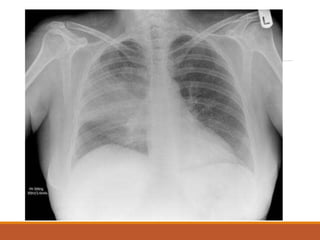

• Imaging : CXR

• #31 bronchopneumonia

• #32 Lobar pneumonia

• #33 ards